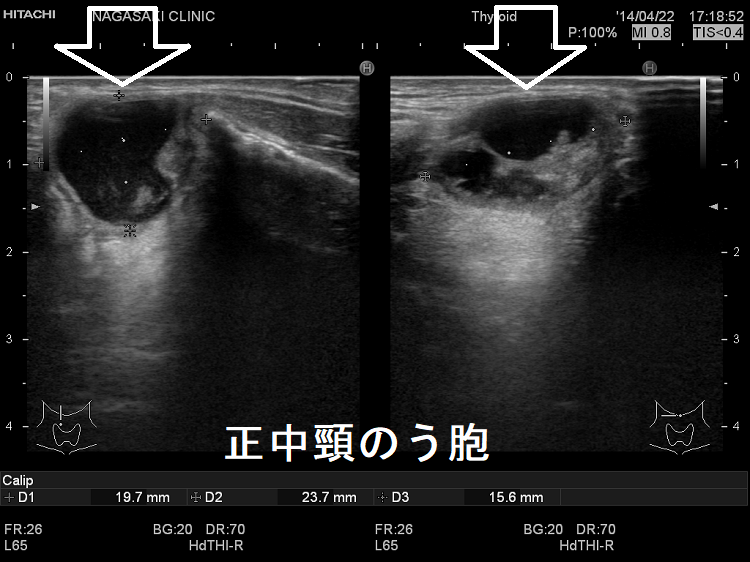

異所性甲状腺の一つ正中頸のう胞(甲状舌管嚢胞)

詳しくは、 正中頸のう胞(甲状舌管嚢胞) を御覧下さい。

正中頸のう胞 超音波(エコー)画像

正中頸のう胞 超音波(エコー)画像 ドプラー

正中頸のう胞(甲状舌管嚢胞) 超音波(エコー)画像 ドプラー